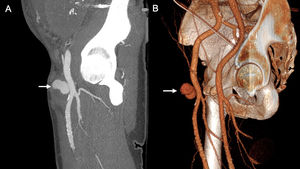

36-year-old woman who had a caesarean section and required re-operation within 24 h due to massive haemoperitoneum secondary to ruptured ovarian endometrioma. She was re-admitted with tympanic abdomen and severe pain. Suspecting active abdominal bleeding, CT angiography of the abdomen and pelvis identified a pseudoaneurysm of the left uterine artery (arrow) in the axial (A) and sagittal (B) maximum intensity projection reconstructions of the arterial phase. During admission, she suffered massive metrorrhagia, so it was decided to re-operate and a bleeding point was detected in the hysterography. However, in view of the situation of haemorrhagic shock during surgery, a subtotal hysterectomy was performed. A few hours later, the patient had significant metrorrhagia with clinical repercussions and the haemodynamic option was finally chosen, which successfully embolised the uterine arteries. After that, her progression was favourable.

A 55-year-old man who had a laparoscopic appendicectomy three days ago, found to have a drop in haemoglobin levels from 11.7 to 7.8 g/dL and abundant serohaematic content in the drainage since the operation. Due to the suspicion of intra-abdominal haemorrhage, CT angiography of the abdomen and pelvis was performed. Coronal maximum intensity projection (A) and 3D (B) reconstructions of the arterial phase showing a pseudoaneurysm arising from the left deep inferior epigastric artery (arrow), probably secondary to arterial injury from the passage of the laparoscopic trocar. The staples are visible at the trocar access point (arrowhead).